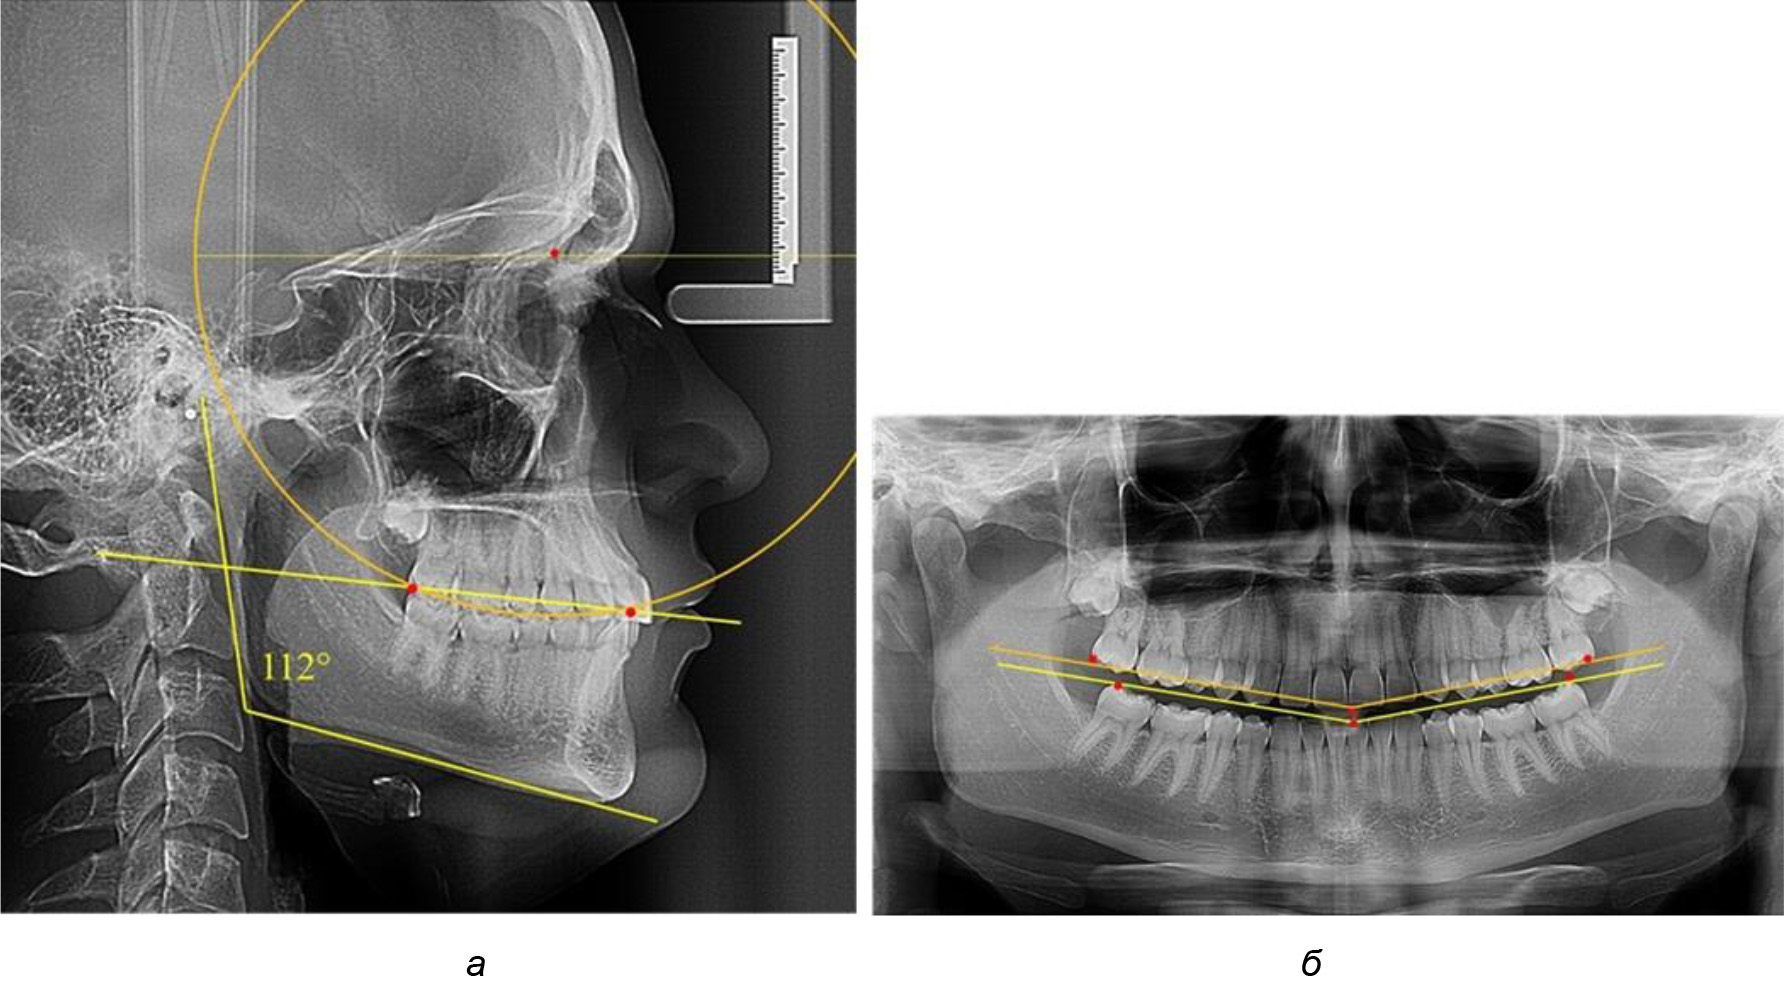

При анализе латеральных ТРГ устанавливали реперный окклюзионные точки в переднем и боковом отделе. Передняя точка устанавливалась на режущем крае нижнего медиального резца, которую в клинике ортодонтии обозначают как vPOcP. Дистальная точка второго нижнего моляра обозначалась как hPOcP. Измеряли расстояние между окклюзионными точками, что определяло сагиттальный размер окклюзионной линии. Использование программ PowerPoint позволило проводить окружность, проходящую по линии смыкания зубов через окклюзионные точки. Измеряли радиус окружности. Учитывая вариабельность размеров окклюзионной линии и радиуса окружности, определяли относительный показатель через отношение радиуса круга к длине сагиттального размера окклюзионной линии. Глубину окклюзионной кривой измеряли от точки наибольшей выпуклости до окклюзионной линии (рис. 1). На ортопантомограмме (ОПТГ) также соединяли окклюзионные точки правой и левой стороны и измеряли глубину окклюзионной кривой от точки наибольшей выпуклости до окклюзионной прямой линии. Результаты глубины кривой Spee сравнивали по данным ТРГ и ОПТГ.

Рис. 1. Метод определения кривой Spee на ТРГ (а) и на ОПТГ (б)

Анализ результатов показал, что глубина кривой Spee в среднем по подгруппе составил (4,12 ± 0,53) мм как при анализе ТРГ, так и ОПТГ.

Деление величины радиуса круга к длине окклюзионной линии составило 1,623 ± 0,02. Таким образом, для определения радиуса окружности, соответствующей кривизне окклюзионного контура боковой ТРГ, необходимо измерить расстояние между передней и задней окклюзионными точками и последующим умножением полученной величины на число Фибоначчи (рис. 2).

Рис. 2. Особенности кривой Spee на ТРГ (а) и ОПТГ (б) у людей с признаками вертикального роста